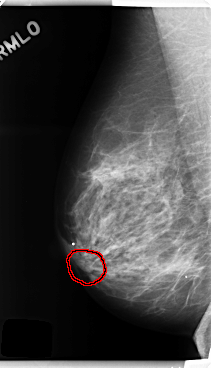

C_0252_1.RIGHT_MLO

FILE: C_0252_1.RIGHT_MLO.OVERLAY

TOTAL_ABNORMALITIES 1

ABNORMALITY 1

LESION_TYPE MASS SHAPE OVAL MARGINS CIRCUMSCRIBED

ASSESSMENT 4

SUBTLETY 3

PATHOLOGY BENIGN

TOTAL_OUTLINES 1

BOUNDARY